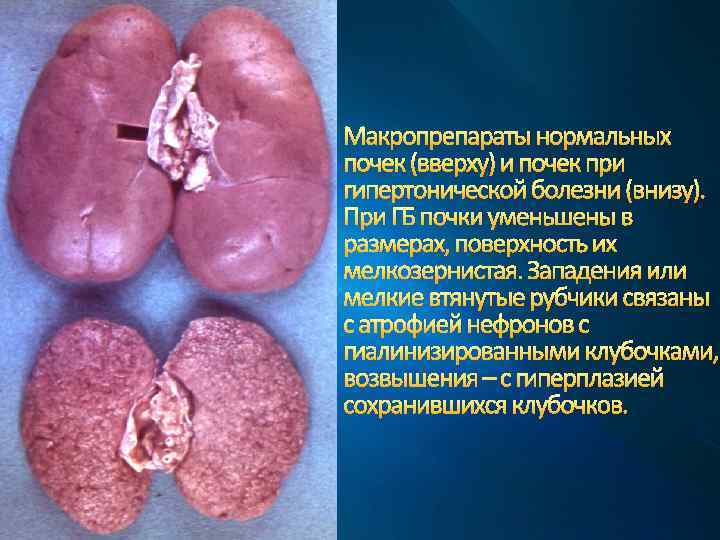

Почечная форма ГБ МАКРОСКОПИЧЕСКИ: Выраженный артериолосклеротический нефросклероз с мелкозернистой поверхностью почек, уменьшением их размеров и истончением коркового вещества

Макропрепараты нормальных почек (вверху) и почек при гипертонической болезни (внизу). При ГБ почки уменьшены в размерах, поверхность их мелкозернистая. Западения или мелкие втянутые рубчики связаны с атрофией нефронов с гиалинизированными клубочками, возвышения – с гиперплазией сохранившихся клубочков.

Почечная форма ГБ МИКРОСКОПИЧЕСКИ: выраженный артериолосклеротический нефросклероз – гиалиноз артериол и клубочков почки, атрофия соответствующих пораженному клубочку канальцев и разрастание на их месте соединительной ткани. Сохранившиеся клубочки компенсаторно увеличены в размерах